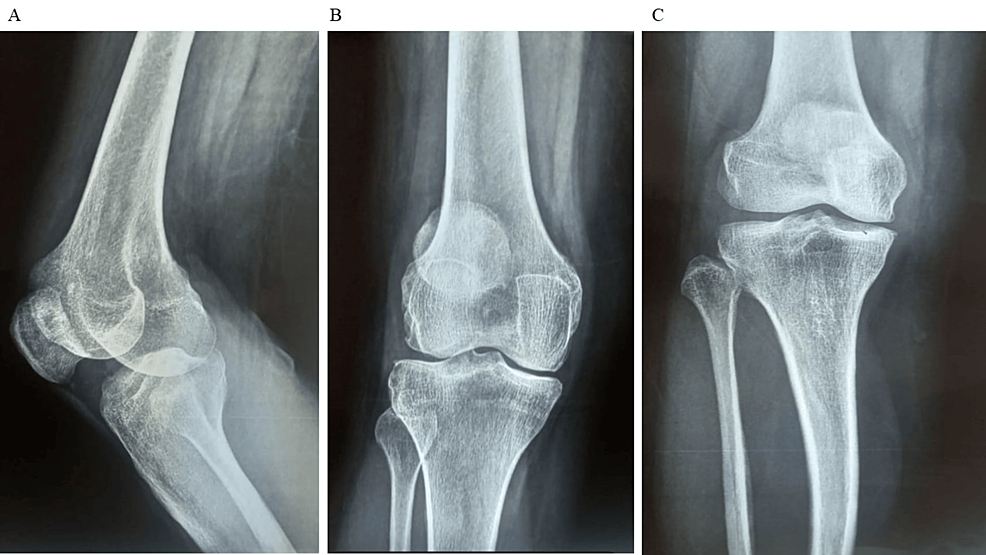

平均WOMAC評(píng)分從基線時(shí)的56.8±11.5下降到六個(gè)月時(shí)的41.2±10.6。此外,還監(jiān)測(cè)了不良事件的發(fā)生情況,報(bào)告了七起不良事件,占參與者的28.0%。這些發(fā)現(xiàn)強(qiáng)調(diào)了該治療在六個(gè)月內(nèi)減輕疼痛和改善功能結(jié)果方面的有效性。下圖2顯示了開始干細(xì)胞治療后骨骼的側(cè)視圖和前后視圖。?

圖2:顯示了開始干細(xì)胞治療后骨骼的側(cè)視圖和前后視圖

圖2:A:干細(xì)胞治療后(側(cè)視圖),B:干細(xì)胞治療后前后位 (AP) 視圖,C:干細(xì)胞治療后前后位 (AP) 視圖。